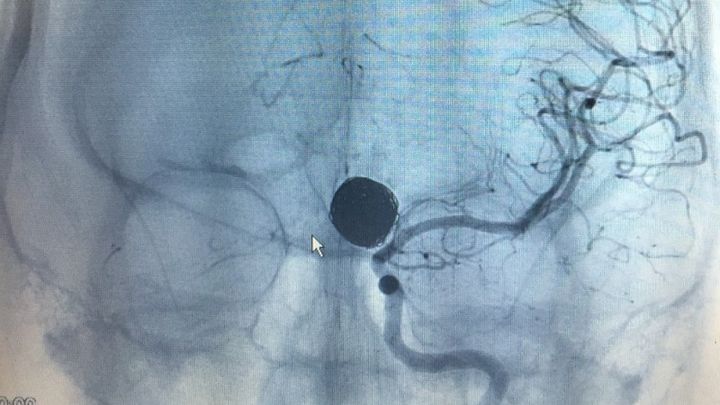

Late evening, on December 13, 2014 my 23 year old, pregnant daughter suffered a ruptured brain aneurysm in Saint Marys, GA. The ambulance took her to Camden County Hospital emergency room for CAT scan. Savannah was then immediately life-flighted to a Neuro Specialty Surgical Center at Baptist Hospital in FL, where she spent 12 days in ICU following brain surgery. Discharged from the hospital on Christmas Day, Savannah's recovery has been miraculous, with no permanent mental or physical damage. She and her husband, Kevin had just purchased their first home together in October 2014. The medical bills are begininning to pile in. As a young married couple with a one year old son and a baby girl on the way, the Steele family could really use some financial assistance for expenses not covered by their insurance. Please consider giving to our Christmas Miracle.